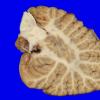

Neuronal Ceroid Lipofuscinosis (NCL) (11)